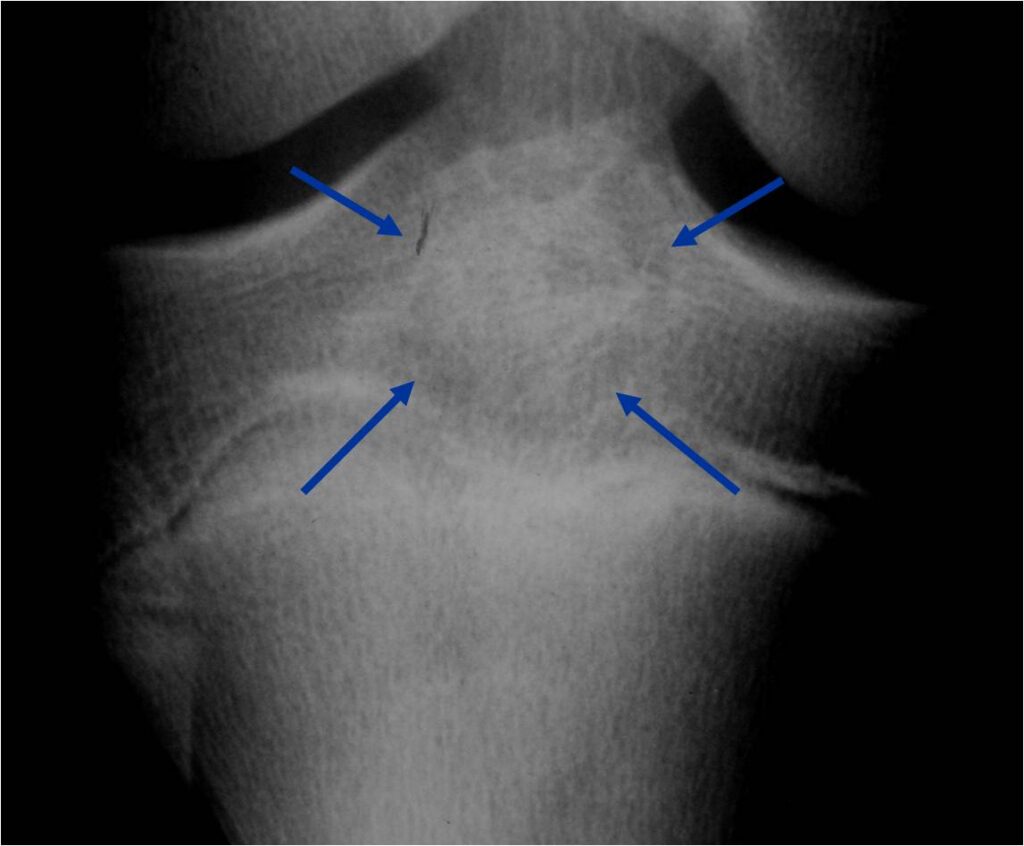

MRI appearance:

- Geographic, well circumscribed lesion in the epiphysis

- Intermediate Signal on T1

- High signal on T2 mixed with low signal areas (low signal areas proposed to be secondary to lysosomal content of highly cellular areas)

- Fluid/Fluid levels demonstrated in tumors that have undergone ABC change (aneurysmal bone cyst change)

- Extensive Surrounding edema is common

- Joint effusion in 30-50% of cases